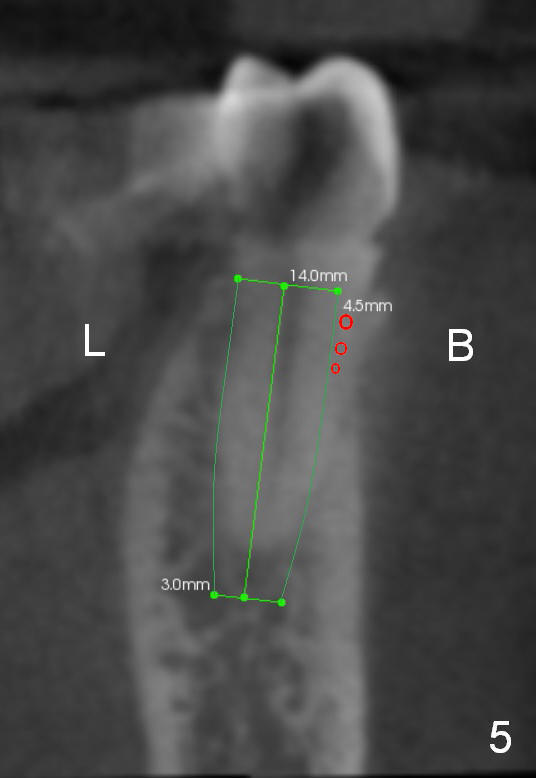

CT sagittal section of a similar case shows that the root is also long, but curved (Fig.4). A 4.5x14 mm implant is slightly longer than the root. The apex of the implant has distance to the underlying nerve (N). The coronal section shows that the implant should be placed lingually (Fig.5 L), since the buccal (B) plate is thin (Fig.6 between arrowheads). The first drill (2 mm) is to be placed lingually (Fig.7 red arrow). When the implant is placed, there should be a buccal gap, to be filled with bone graft (Fig.5 red circles).